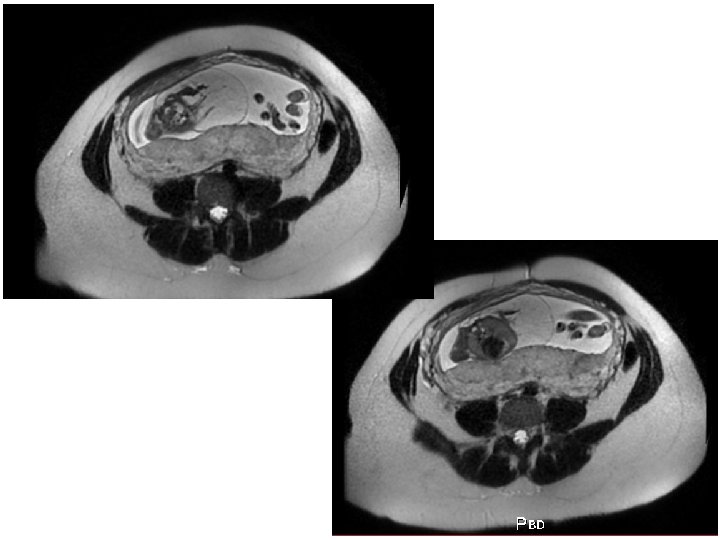

IRM foetale • Pas en 1ère intention • Indiquée à partir de la constatation d’une anomalie fœtale à l’échographie anténatale • IRM cérébrale fœtale +++ • IRM pour pathologie fœtale en dehors du système nerveux : – Thorax – Bilan de masse (bilan anatomique précis)